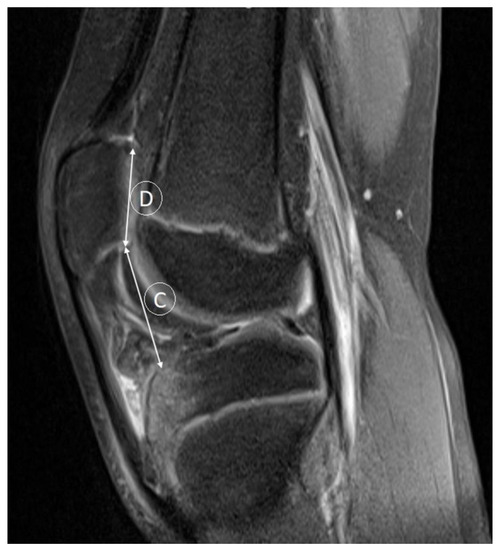

- Verhulst, F.V.; van Sambeeck, J.D.P.; Olthuis, G.S.; van der Ree, J.; Koeter, S. Patellar height measurements: Insall-Salvati ratio is most reliable method. Knee Surg. Sport. Traumatol. Arthrosc. 2020, 28, 869–875. [Google Scholar] [CrossRef] [PubMed]

- Kurowecki, D.; Shergill, R.; Cunningham, K.M.; Peterson, D.C.; Takrouri, H.S.R.; Habib, N.O.; Ainsworth, K.E. A comparison of sagittal MRI and lateral radiography in determining the Insall-Salvati ratio and diagnosing patella alta in the pediatric knee. Pediatr. Radiol. 2022, 52, 527–532. [Google Scholar] [CrossRef] [PubMed]

- Thévenin-Lemoine, C.; Ferrand, M.; Courvoisier, A.; Damsin, J.P.; Ducou le Pointe, H.; Vialle, R. Is the Caton-Deschamps index a valuable ratio to investigate patellar height in children? J. Bone Jt. Surg. 2011, 93, e35. [Google Scholar] [CrossRef] [PubMed]